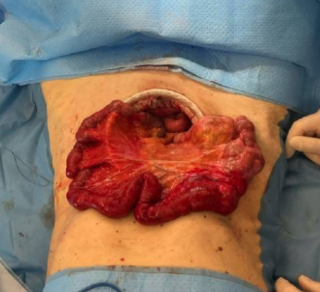

Case presentation

A 55-year-old overweight man presented with one week of right-sided abdominal pain with recent worsening despite outpatient medical therapy. He was hemodynamically stable but had right upper quadrant tenderness and localized guarding. Laboratory testing showed elevated C-reactive protein with a normal leukocyte count and normal liver biochemistry. CT demonstrated inflammatory fat stranding of the right greater omentum with a hyperdense rim, consistent with right-sided omental infarction (Figure 1). Because pain persisted despite conservative management, diagnostic laparoscopy was performed and confirmed ischemic omentum with hemorrhagic peritoneal fluid (Figure 2), and a normal gallbladder and appendix. Laparoscopic omentectomy was completed without complications. Histopathology confirmed omental infarction (Figure 3). The patient was discharged on postoperative day 1 and remained asymptomatic at 6-week follow-up.